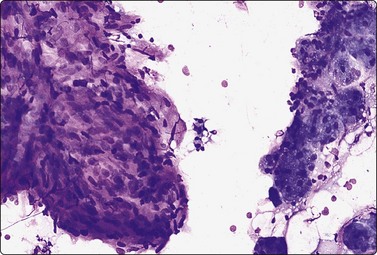

image image

Fig. 4.9 Nasopharyngeal carcinoma (undifferentiated, lymphoepithelial type, WHO type III)

Loose clusters of undifferentiated epithelial cells with vesicular nuclei, prominent nucleoli and pale fragile cytoplasm. Background of lymphocytes. (A, MGG, HP; B, H&E, HP).

Criteria for diagnosis (undifferentiated carcinoma nasopharyngeal type (UCNT)/WHO type III/lymphoepithelial carcinoma)

Undifferentiated malignant cells, single and in clusters,

Variable amount of pale, fragile cytoplasm,

Large vesicular nuclei with prominent central nucleoli,

Admixture with, and background of, lymphoid cells, often with prominent plasma cells,

Ancillary tests: neoplastic cells positive for cytokeratin, negative for lymphocyte markers. EBV-associated nuclear antigen.

Nasopharyngeal carcinoma (NPC) is a clinicopathologic entity different from other squamous cell carcinomata of the head and neck. It is distinguished by its particular histology, geographic distribution, relationship to Epstein-Barr virus, and the absence of an alcohol or tobacco etiological relationship. A proportion of NPCs show squamous differentiation and the cytological pattern of non-keratinizing squamous cell carcinoma (squamous cell carcinoma/WHO type II) (Fig. 4.8). Keratinized cells (WHO type I) are uncommonly found. The majority of NPC are poorly differentiated or undifferentiated. Cells from undifferentiated NPC (UCNT, WHO type III) form loose clusters with no specific microarchitectural pattern, and are usually mixed with lymphoid cells. In the ‘lymphoepitheliomatous’ type (Schmincke-Regaud) the cells tend to be less cohesive, resembling Hodgkin’s disease or large cell non-Hodgkin lymphoma. However, in NPC, the malignant cells are still clustered and have more abundant pale cytoplasm contrasting with the lymphoid cells in the background (Fig. 4.9). Plasma cells are frequently found among the lymphoid cells. Immunostaining for cytokeratin and a pan-lymphocyte marker is helpful. Epstein-Barr virus-associated nuclear antigen is demonstrable by anticomplement immunofluorescence in undifferentiated tumors. Other patterns of growth may occur and may cause diagnostic problems; for example, spindle cell forms may be difficult to recognize as carcinoma.

NPC frequently presents to the cytologist as a lymph node metastasis in the neck without a known primary. Cytological recognition is important since the primary is often clinically occult.